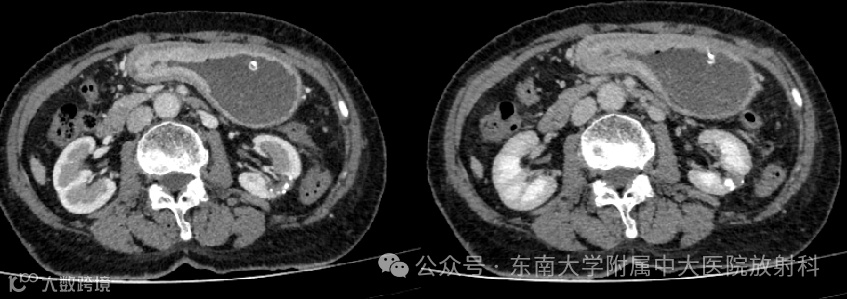

病例1

女,74岁 -

主诉:进食后腹胀呕吐1月 -

现病史:患者1月前无明显诱因下出现腹胀症状,稍进食即感腹胀,伴呕吐,呕吐物为胃内容物,无特殊臭味,未见胆汁。今日至我院就诊,完善胃镜检查示:胃腔内见大量黄色食物潴留,胃窦变形,胃窦似见一新生物,黏膜僵硬,表覆溃疡,因食物残渣覆盖,无法窥清。考虑诊断:1、胃潴留2、胃窦新生物?。现为求进一步诊疗,门诊拟“胃潴留”收住入院。病程中,患者神志清,精神可,饮食睡眠一般,二便正常,近期无体重明显变化

影像学检查